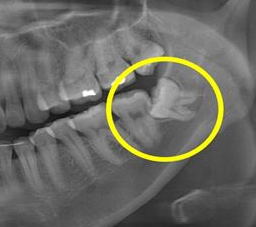

"사랑니가 바로 클루지다."

다시 말해,

"인간이 진화하는 과정에서 따라온 유용하지 않은 부산물"

정도로 보면 될 것이다.

사실 사랑니는 그저 클루지의 한 예시에 불과하다.

진정한 클루지는 바로 '인간의 뇌'이다.